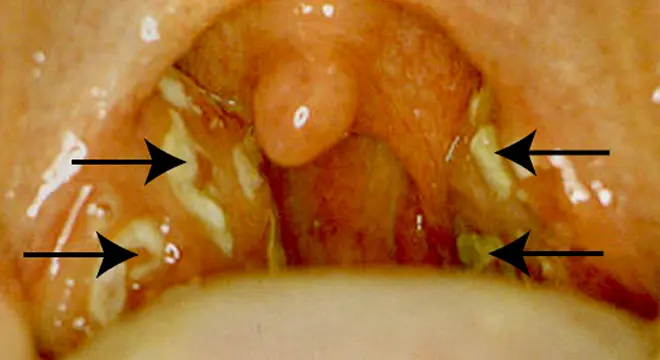

Die Angina tonsillaris ist eine Infektion der Mandeln, die sich im Rachen befinden. Die Mandeln sind Teil des Immunsystems und helfen, den Körper vor Infektionen zu schützen. Eine Mandelentzündung wird in der Regel durch Viren verursacht, aber auch Bakterien können die Ursache sein.

- Mandelbeläge (weiße oder gelbe Flecken auf den Mandeln)